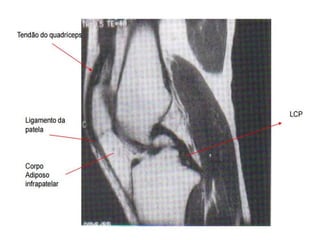

SAGITAL

QUADRICEPS TENDON

PATELLA

PATELLAR

TENDON

ANTERIOR CRUCIATE

LIGAMENT

POSTERIOR CRUCIATE

LIGAMENT Scan level